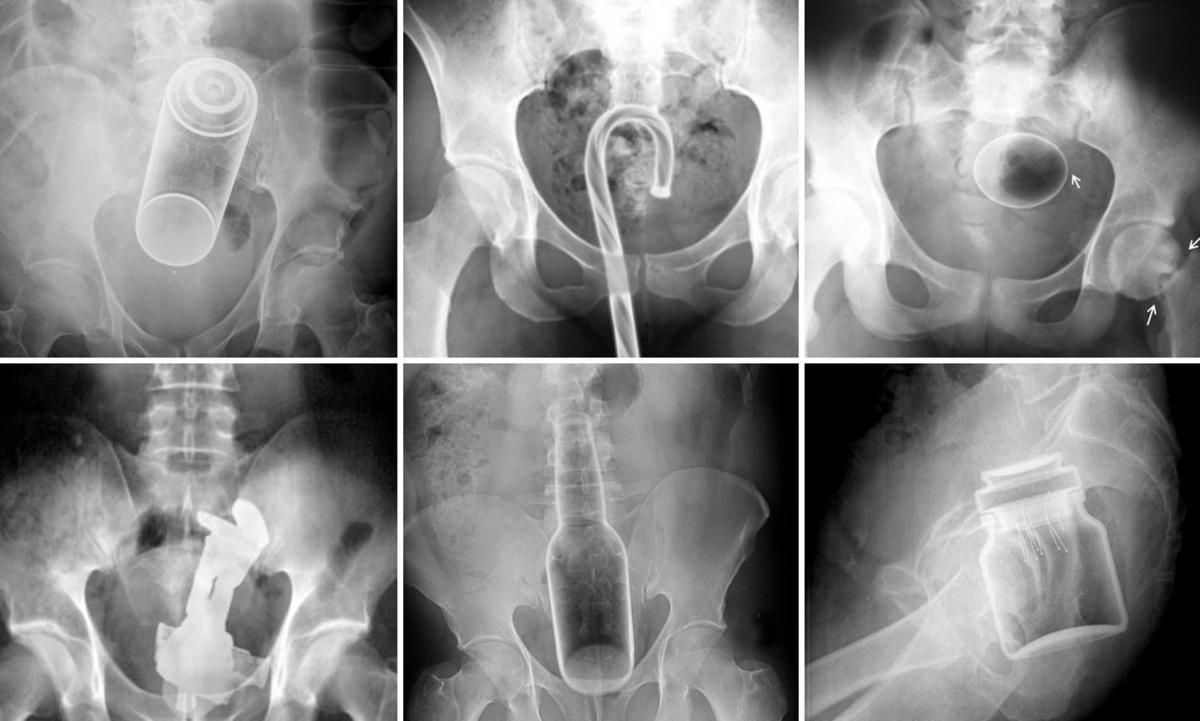

Ztracené či zaseknuté předměty v tělních dutinách jsou zdrojem mnoha a mnoha historek z nočních chirurgických pohotovostí, které lékaři ideálně demonstrují na velmi výmluvných snímcích z rentgenu. Tyto nehody se dějí jak dámám, tak labužnickým pánům, protože hladká svalovina je velmi elastická a lidské tělo dokáže pojmout neuvěřitelné věci.

Lékaři tak musejí vytahovat nejen vibrátory (nedopatřením zajeté příliš hluboko), ale také nemálo předmětů běžné denní potřeby či zeleninu, jež mají alespoň zhruba falický tvar. Ovšem zdaleka nejčastějšími pacienty nejsou ani tak milovníci kvalitně zašpuntovaného těla, jako spíše oběti nehod. Lékaři tak obvykle „loví“ tampony, na které majitelka zapomněla, nebo kondomy, jež se při sexu shrnuly – a už se je nepodařilo najít.